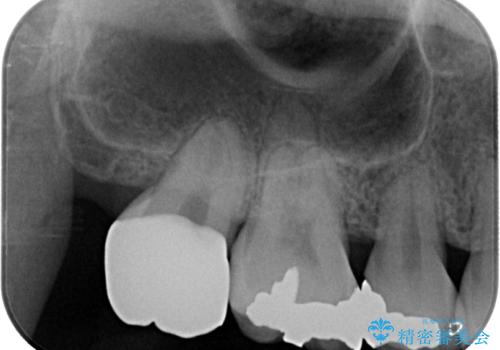

セラミッククラウンの適合はレントゲン写真からも分かる通り、境界がぴったりと合った、高適合のものとなりました。